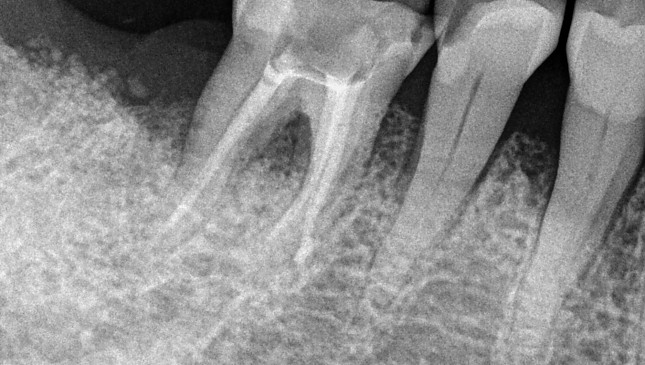

치아살리기 치료 전후 사진

잇몸재생교정 치료 전후사진

잇몸 전체가 무너져 동시다발적으로 죽어가던 치아들을 한꺼번에 살려 냅니다.